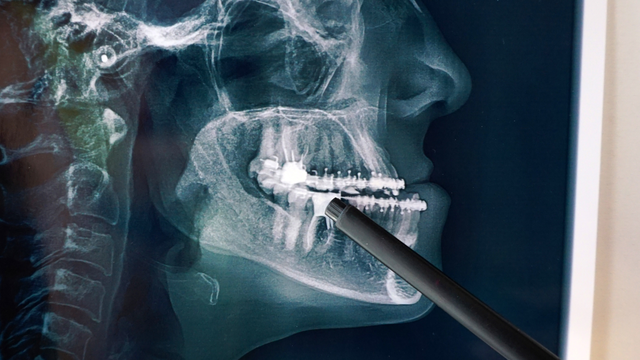

Tổng hợp các bài viết sức khỏe chủ đề chụp ct